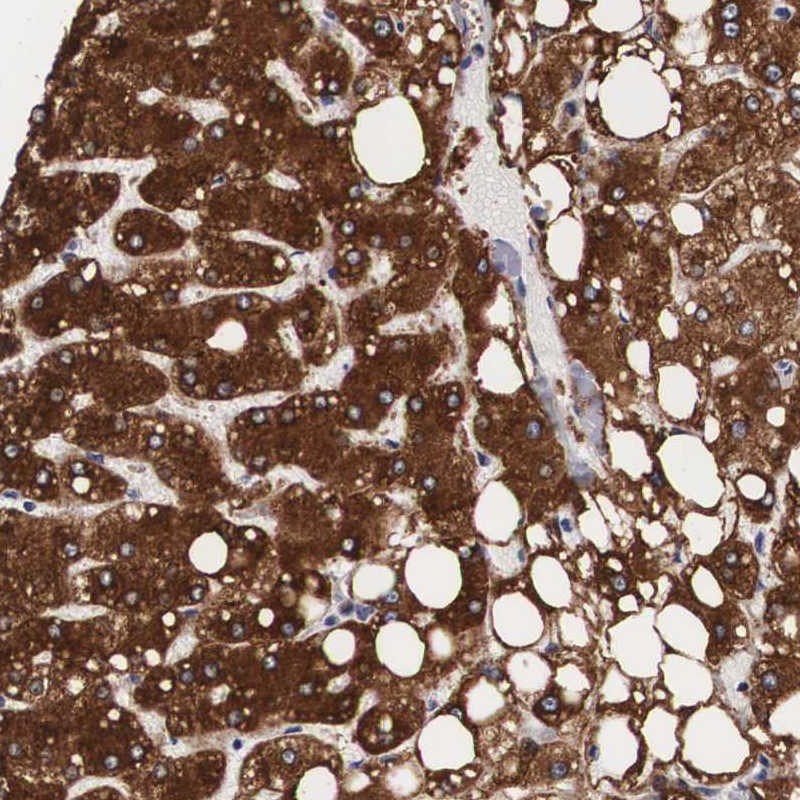

Immunohistochemical staining of human liver shows strong cytoplasmic positivity in hepatocytes.